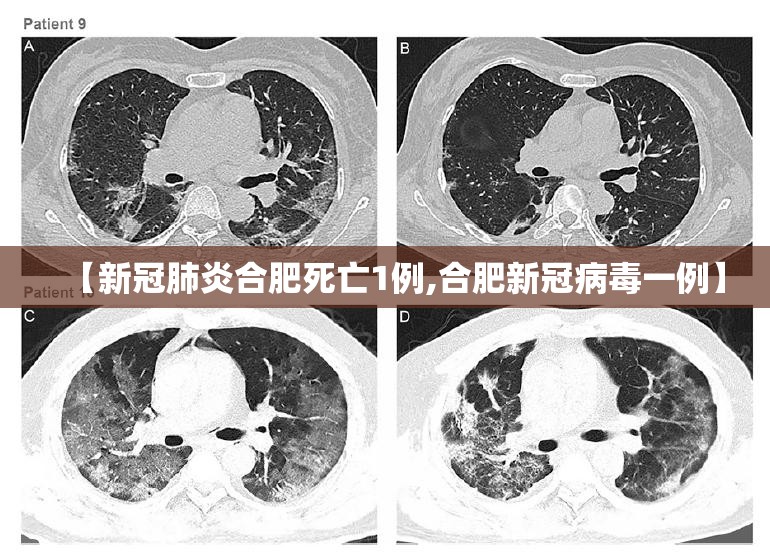

新型冠状病毒肺炎的死亡原因主要有以下几点:急性呼吸窘迫:感染新冠病毒后,患者可能会出现急性呼吸窘迫,表现为非常严重的呼吸困难,这是导致死亡的重要原因之一。休克:部分患者由于病情严重,可能会出现休克症状,进一步危及生命安全。

一项来自德国的大规模新冠病例尸检研究报告显示,86%的病例死亡根本原因是新冠肺炎。常见的直接死因包括弥漫性肺泡损伤、急性呼吸窘迫综合征、多器官衰竭、细菌重复感染和肺栓塞等。在其余14%的尸检病例中,新冠肺炎是一种伴随疾病。大部分患者都死于心脏病、心肌梗死等循环性疾病或者吸入性肺炎等呼吸性疾病。